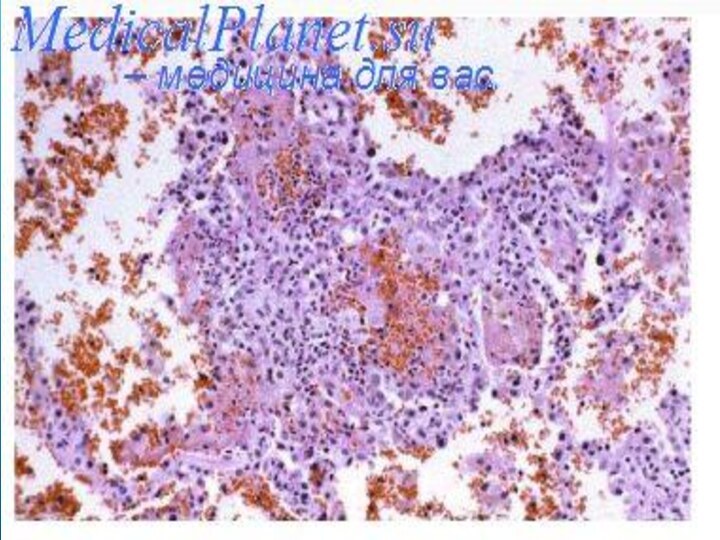

Раздел: Фотоэссе